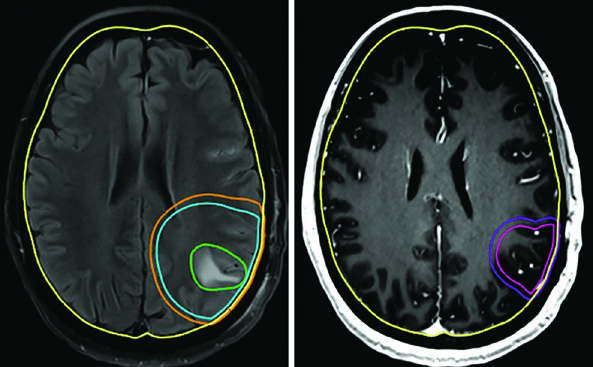

O ponto central é este: a delineação precisa tanto dos volumes-alvo quanto dos órgãos de risco determina qual técnica será mais vantajosa para cada paciente. E para isso, a corregistração de RM diagnóstica no CT de planejamento não é opcional — é fortemente recomendada. As sequências T1 pós-contraste e FLAIR permitem visualizar tanto o tumor residual quanto o edema perilesional, enquanto sequências T1 simples e 3D-T2/CISS ajudam a delinear estruturas como hipocampo e nervos cranianos. Para mais contexto sobre os princípios gerais de delineamento, confira nosso guia completo sobre delineamento de volume alvo na radioterapia.

Pacientes com astrocitoma de alto grau e oligodendroglioma passam por ressecção cirúrgica máxima para diagnóstico, caracterização molecular e citorredução. O tratamento padrão combina radioterapia conformacional fracionada com quimioterapia — seja concomitante, adjuvante ou ambas.

A dose padrão para gliomas de alto grau é de 59,4–60 Gy com fracionamento convencional. Para pacientes idosos, frágeis ou com performance status limitado, esquemas hipofracionados são uma alternativa validada: 40,05 Gy em 15 frações ou até 25 Gy em 5 frações, com margens reduzidas (0,5–1 cm). A tabela a seguir resume os volumes recomendados por tipo tumoral.

Pacientes idosos ou com performance status comprometido representam um desafio particular. O esquema de 40 Gy em 15 frações funciona bem quando há pouco volume FLAIR fora do tumor captante — o GTV inclui cavidade de ressecção, tumor residual e nódulos satélites na T1 pós-contraste, com expansão de CTV de apenas 1,0 cm e restrição anatômica ao tentório.

Alguns erros recorrentes no planejamento de tumores malignos do SNC merecem destaque. O mais comum é aplicar expansões isotrópicas sem respeitar as barreiras anatômicas. O CTV de um glioblastoma frontal não deve cruzar a linha média — a menos que o joelho do corpo caloso esteja em risco, caso em que essa estrutura deve ser explicitamente incluída. Outro erro é ignorar a diferença entre as sequências de RM: o GTV1 deve ser baseado no FLAIR (edema perilesional), enquanto o GTV2 usa a T1 pós-contraste (doença captante residual).